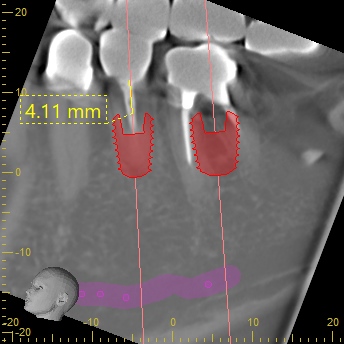

当院では事前にCTデータを用いたコンピュータシミュレーションを徹底して行います。

州デンタルオフィスの強み:ガイデッドサージェリー

当院では全症例において「ガイデッドサージェリー」を使用します。これは、事前のシミュレーション通りにインプラントを植立するための「マウスピース型のガイド」を使用する手法です。

これにより、フリーハンドに比べて計画とのズレが極めて少なく、安全性が高いのはもちろん、無駄な動きがないため手術時間を短縮できます。「手術が怖かったけれど、あっという間に終わって驚いた」と仰る患者さんが多いのも、この精密な事前準備があるからです。

・ガイデッドサージェリー: CTデータに基づき作成されたガイドを使用し、あらかじめ決めた位置・深さ・角度に正確にインプラントを導くシステム。